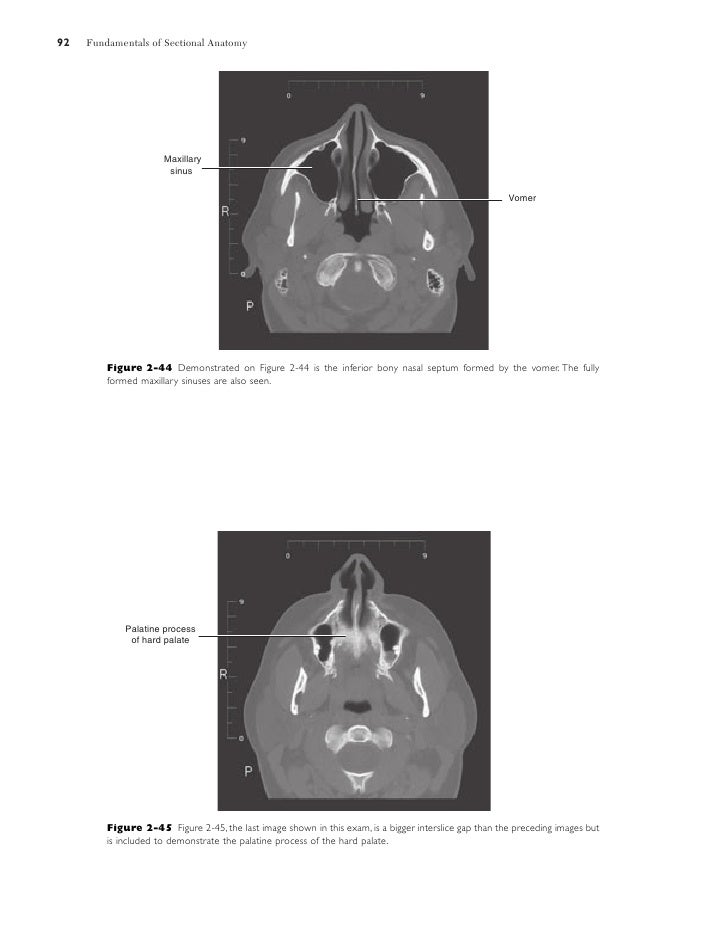

Vomer Anatomy

The vomer ˈ v oʊ m ər is one of the unpaired facial bones of the skull.

It is unpaired and lies in the midline between the two nasal cavities. The vertical plate of the vomer bone articulates with the perpendicular plate of the ethmoid bone to form the bony nasal septum. The vomer is one of the facial bones and forms the postero inferior part of the bony nasal septum.